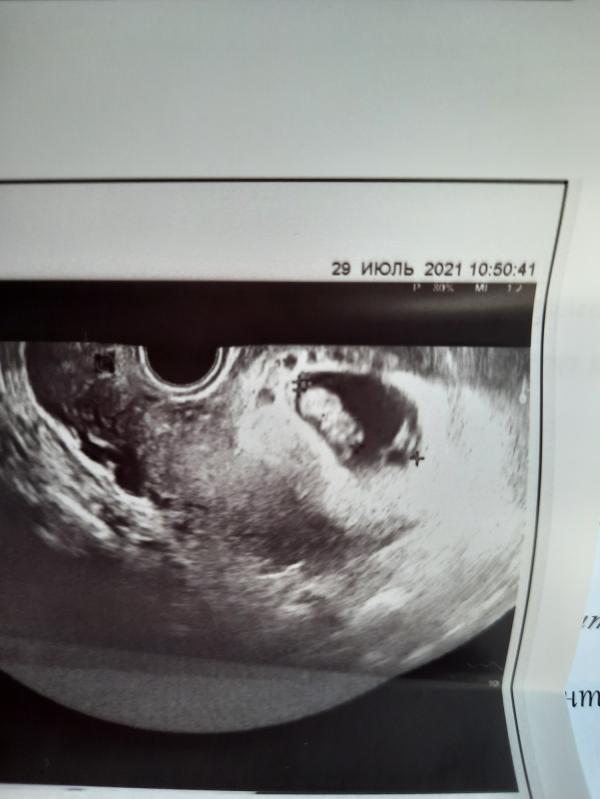

Мутные воды это очень плохо? УЗИст сказала, что это означает перенесённое ОРЗ

В заключении написано косвенные признаки ВУИ

У меня все анализы всегда все было хорошо., но после прокола пузыря - то отошли зелёные воды , в итоге экстреннное кс, тк малыш стал задыхаться . Я перенесла ковид на 11 неделях